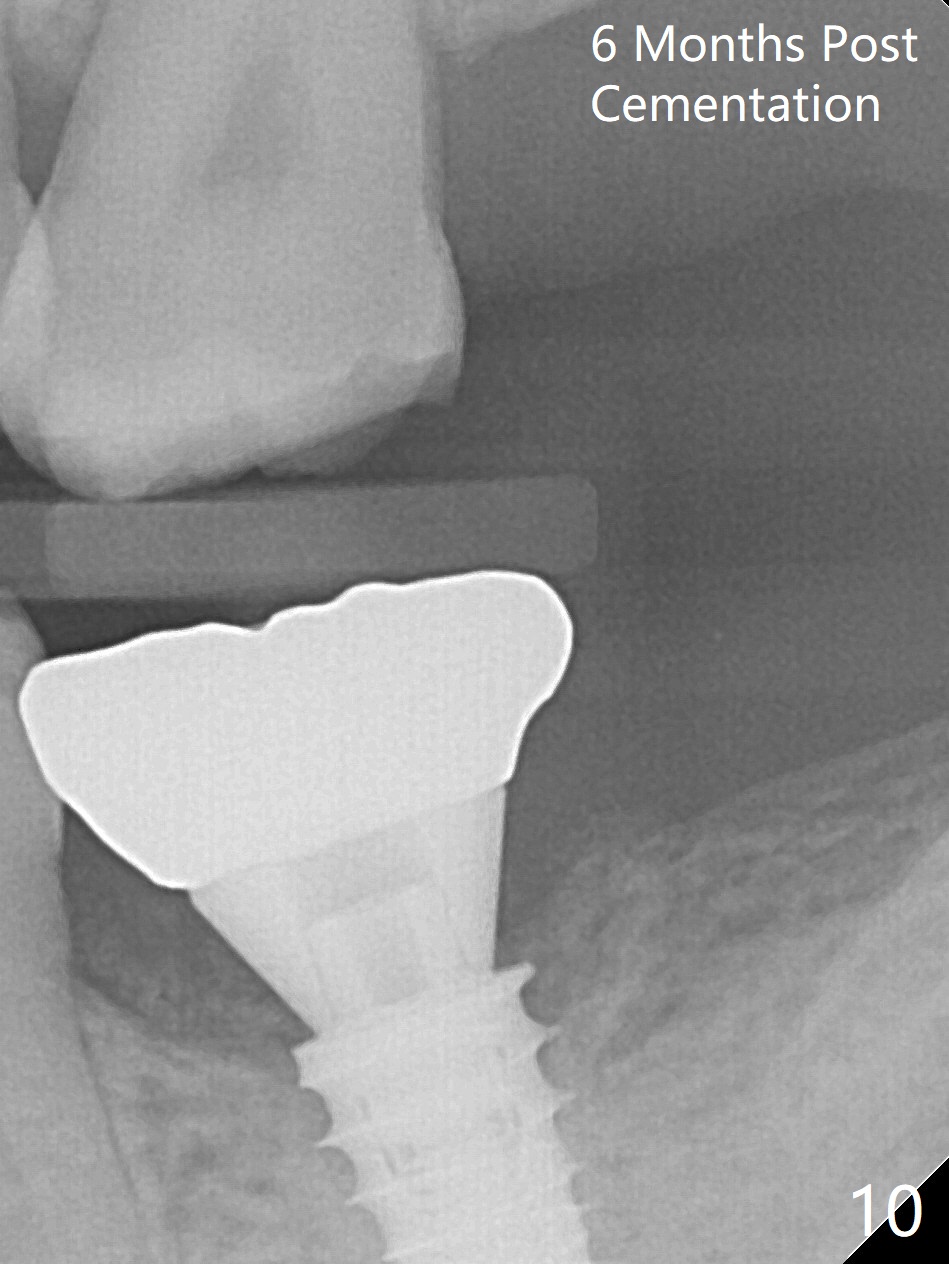

Three months postop, there is no bone resorption, while the bone graft seemingly remains in place (Fig.8).  Bony trabecule has grown into the distal socket 6 months post cementation (10 months postop, Fig.10).